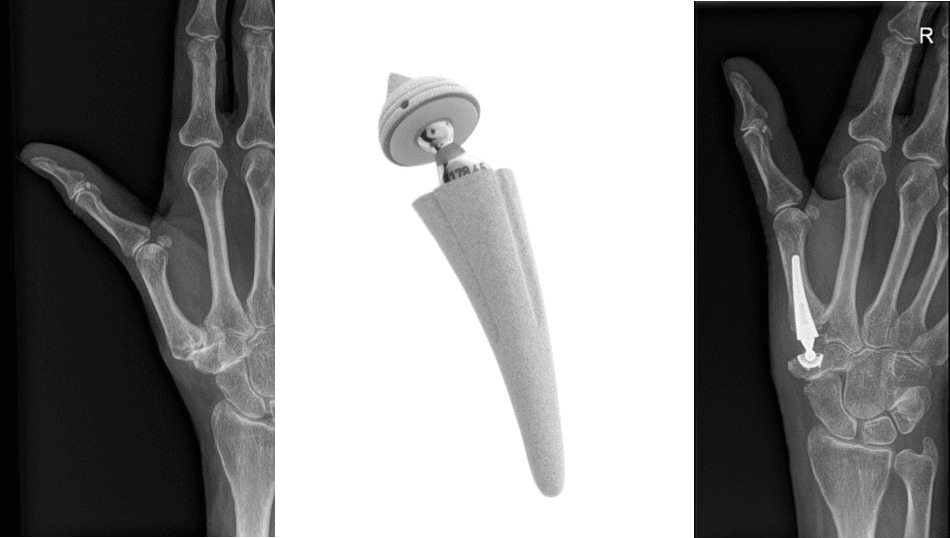

Wanneer de hierboven beschreven maatregelen falen of bij een ernstige arthrose kan een ingreep een oplossing bieden. Een duimprothese is een kunstgewricht dat het beschadigde deel (kraakbeen) van het duimgewricht vervangt. Er wordt daarvoor een gebogen insnede gemaakt aan de duimbasis. Het versleten kraakbeen wordt verwijderd en vervangen door een nieuwe glijlaag in de vorm van een duimprothese.

- Luxatie: De duimprothese bestaat uit een kommetje en een kopje op een steel. Het kopje kan luxeren of uit de kom schieten. Het kopje moet dan terug in de kom geplaatst worden. Heel zelden is hiervoor een nieuwe operatie nodig.